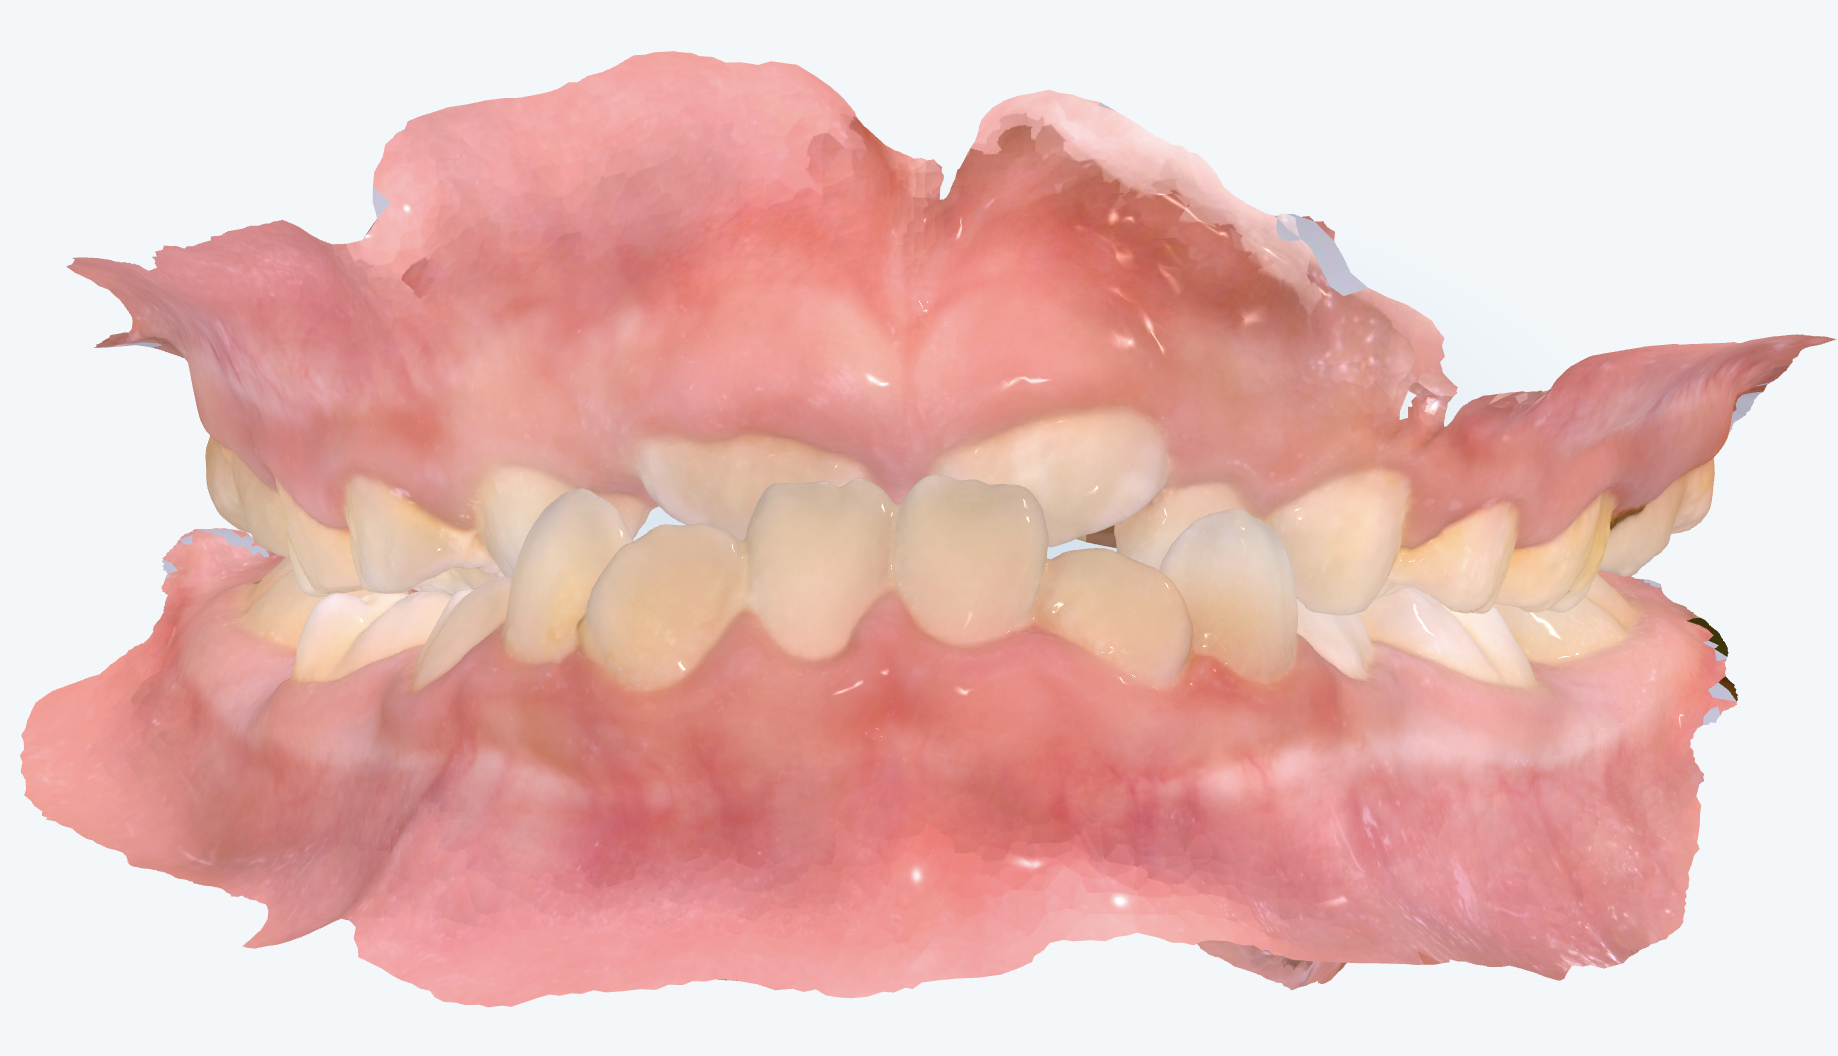

初診時の画像診断

永久歯の前歯が反対咬合になっていました。

上の歯並びはガタガタがあり、左上の前から2番目の歯が生えるスペースがありません。